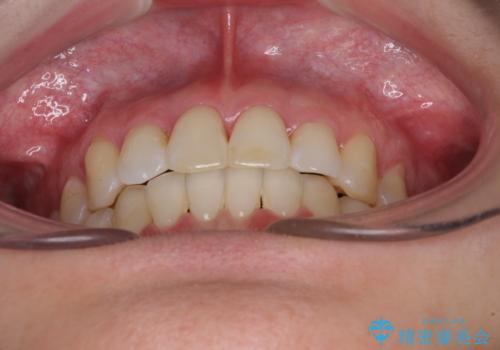

上下の骨幅を改善したことで、スムーズに歯列矯正を行うことができました。

奥歯の咬み合わせを改善する必要があったため、治療は長期化しましたが、きっちりと仕上げることができました。